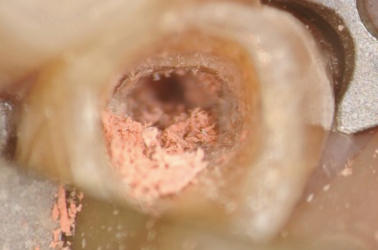

Cotton Pellet on Top of Gutta Percha

Close Up View

Gutta Purcha Removed to 12mm with Ultrasonic

Close Up View